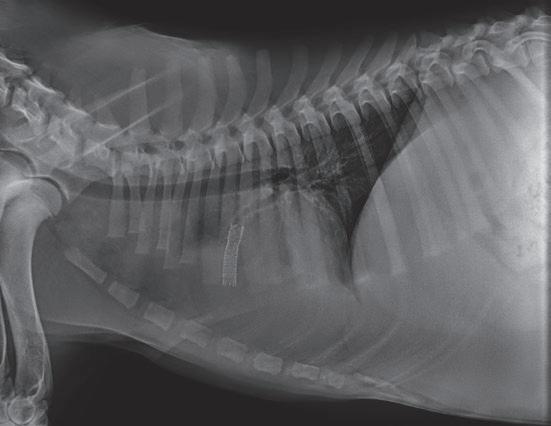

La responsabilidad de los artículos, reportajes, comunicados, etc. recae exclusivamente sobre sus autores. El editor sólo se responsabiliza de sus artículos o editoriales. La ciencia veterinaria está sometida a constantes cambios. Así pues es responsabilidad ineludible del veterinario clínico, basándose en su experiencia profesional, el correcto diagnóstico de los problemas y su tratamiento. Ni el editor, ni los autores asumen responsabilidad alguna por los daños y perjuicios, que pudieran generarse, cualquiera que sea su naturaleza, como consecuencia del uso de los datos e información contenidos en esta revista. De acuerdo con la normativa vigente en materia de protección de datos Grupo Asís Biomedia, SL., es responsable del tratamiento de sus datos personales con la finalidad de enviarle comunicaciones postales de nuestras revistas especializadas, así como otras comunicaciones comerciales o informativas relativas a nuestras actividades, publicaciones y servicios, o de terceros que puedan resultar de su interés en base a su consentimiento. Para ello, Grupo Asís podrá ceder sus datos a terceros proveedores de servicios de mensajería. Podrá revocar su consentimiento, así como ejercer sus derechos de acceso, rectificación, supresión, oposición, limitación y portabilidad enviando un correo electrónico a protecciondatos@grupoasis.com, o una comunicación escrita a Grupo Asís en Centro Empresarial El Trovador, planta 8, oficina I, Plaza Antonio Beltrán Martínez 1, 50002, Zaragoza (España), aportando fotocopia de su DNI o documento identificativo sustitutorio e identificándose como suscriptor de la revista. Asimismo, si considera que sus datos han sido tratados de forma inadecuada,